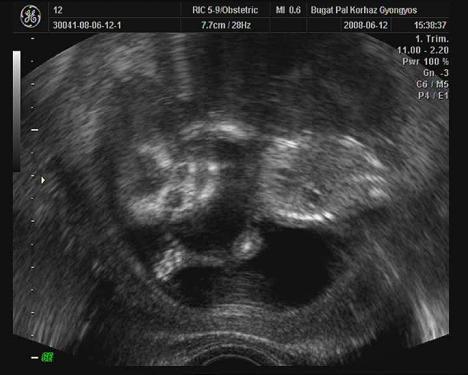

Rakok még két normál uh-s képet.

Itt mérik a kukit(remélhetöleg):

Kép

Kis ufó, szemböl, kezei meg a feje mellett:

A babának bizony ott a "3.lába"! PASIURALOM!!!!!!!!!!!!!!!